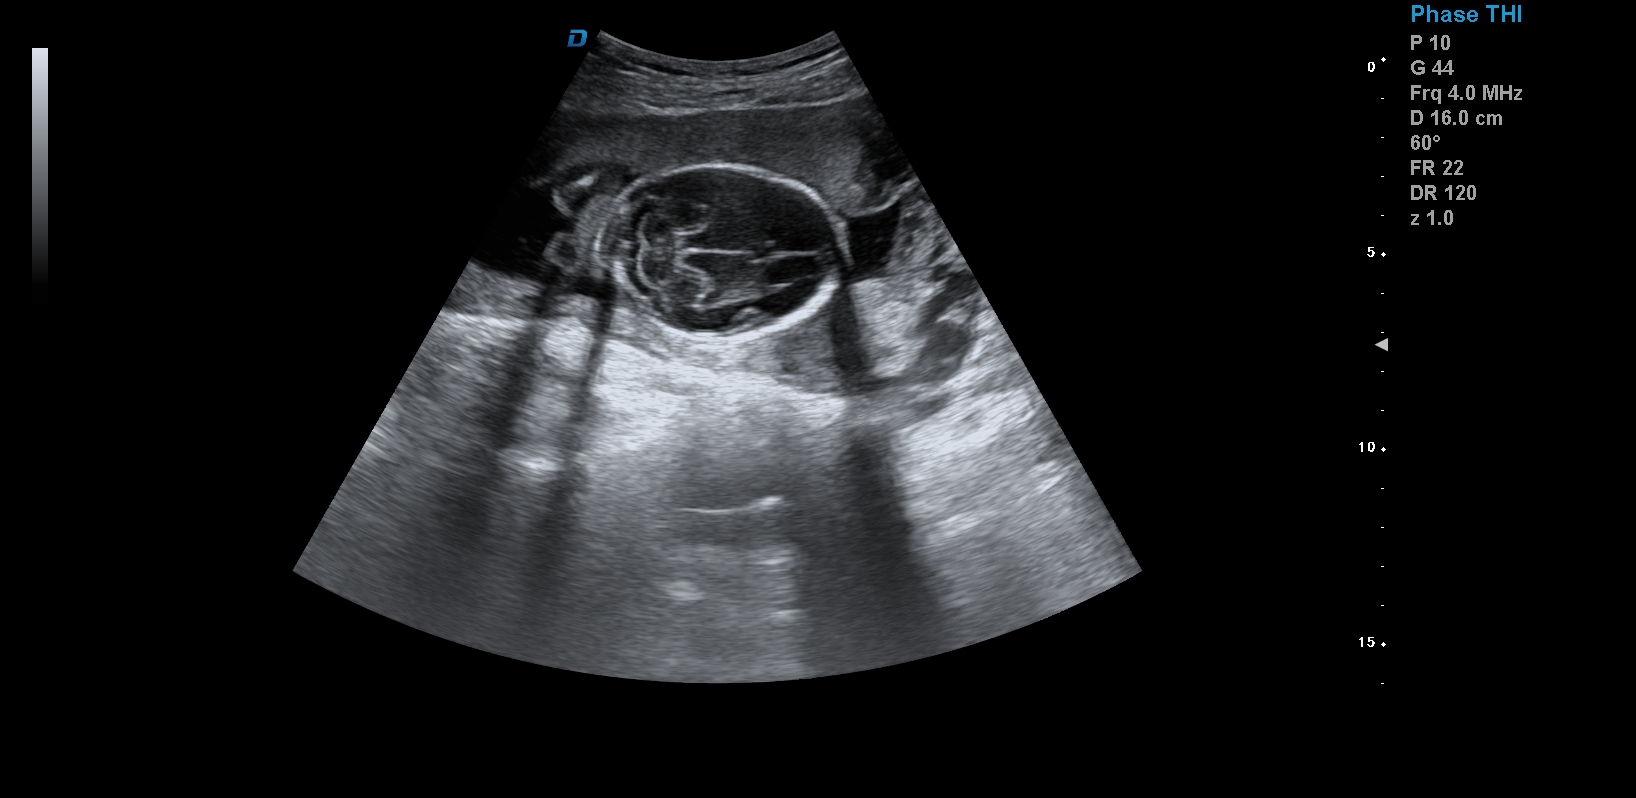

首先,四維彩超檢查是采用高清晰度的彩超儀對胎兒進行各個心臟器官及組織的一次全面檢查,可以立體顯示胎兒的發育情況,胎兒在子宮內的任何狀態都可以觀察到。對胎兒畸形能夠早診斷,及時地做出相應的措施,以達到優生優育的標準。

四維彩超不但成像清晰,更是在三維的基礎之上附加時間這個矢量。這就在排畸的同時能時刻觀察寶寶在宮內的一舉一動,吃手指、打哈欠、吮吸……寶寶在宮內憨態可掬,讓孕媽媽母愛井噴,幸福不已。這也是孕媽媽們選擇四維的主要原因,試想,誰不想在辛苦懷孕期間提前看一看自己寶寶的模樣呢?

1、四維彩超是目前先進的彩色超聲技術.能直觀立體現實人體器官動靜態三維結構,一定程度上提高臨床診斷的準確性。

3、清晰成像:采用先進的超聲成像技術,擁有高清晰,高分辨率、高精確度優點,能清晰看到包括生殖器、內臟器官在內的胎兒的各個部位發育情況.

四維彩超最佳時間是24-26周。這個時候胎兒結構發育完善,可觀察到大多數的胎兒畸形。胎兒30周左右最好再去做一次四維彩超,因為胎兒結構是一個逐漸發育的過程,畸形沒有發展到一定程度可能不能被檢查到。